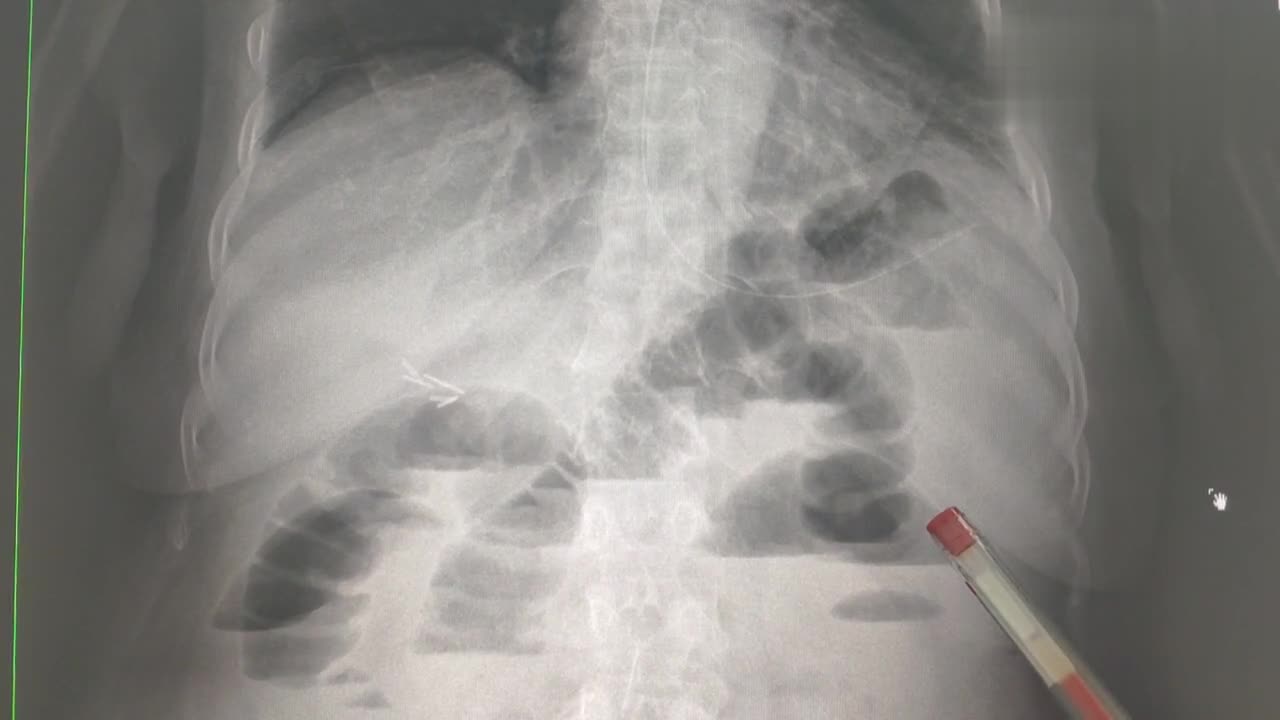

肠梗阻x线图片

一位典型肠梗阻患者的x线平片,可以看到明显的扩张积气肠管.

腹部x光片显示肠梗阻